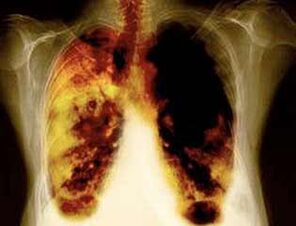

Lungenläsionen bei der Verwendung von Nikotin